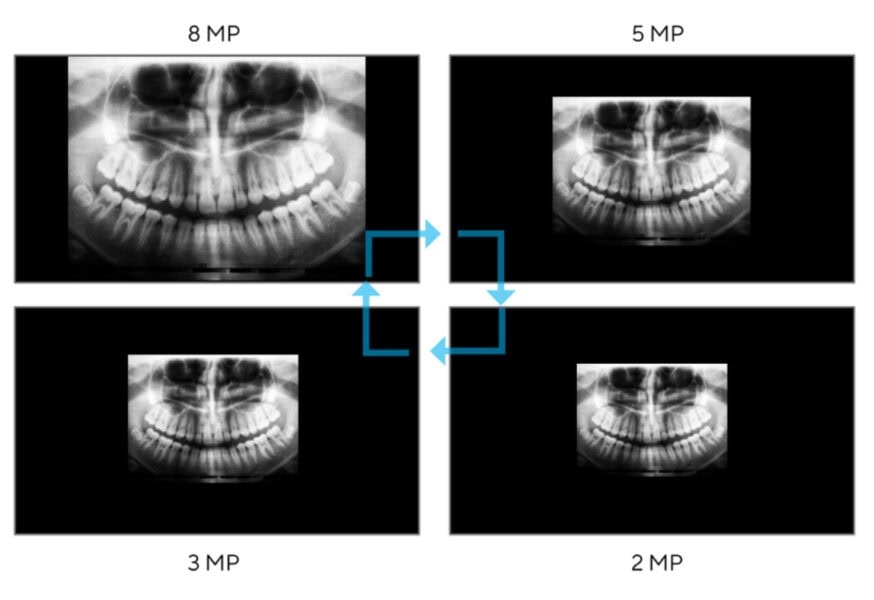

8MP Yüksek Çözünürlük

ASUS HealthCare Ekranlar, 8 megapiksele varan görüntüleri yüksek çözünürlükle sunar. Benzer boyuttaki 2 megapiksel ekranlara göre dört kat daha fazla piksel yoğunluğu ve %300’e kadar daha fazla ekran alanı sağlar. Bu da keskin ve ayrıntılı görsellerin keyfini çıkaracağınız anlamına gelir. Ayrıca, monitörün ortaya koyduğu geniş ekran alanı birden fazla işle uğraşırken kolaylık sağlayarak tüm görsellerin ekrana sığmasını ve hatta birden fazla görüntünün tek ekranda yan yana görüntülenmesini sağlar.

Uygun Ekran Çözünürlüğü

Farklı tıbbi görüntüleme yöntemlerinde, tıbbi görüntülerin sunumu hem boyut hem de görüntülenen bilgi miktarı açısından farklılık gösterebilir. ASUS HealthCare monitörler, ekrandaki noktadan noktaya değişen tıbbi görsel kaynakları görüntülemek için birden fazla çözünürlük kullanabilir.